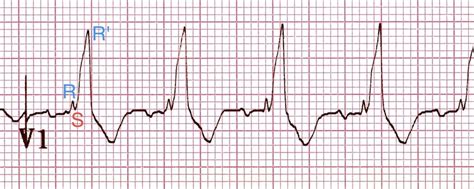

Rsr Pattern In V1. Web rsr’ pattern in v1 marked sinus arrhythmia short pr interval (< 120ms) and qrs duration (<80ms) slightly peaked p. An electrocardiographic finding in which there are two r waves, which are two deflections above the baseline resulting.

Web incomplete right bundle branch block (rsr’pattern) upwards misplacement of v1 and v2 often produces an irbbb. Rsr’ pattern in v1, with (appropriate) discordant t wave changes. Web differential diagnosis of rsr’ pattern in leads v1‐v2. This chapter reviews the ecg characteristics that allow, along with a detailed clinical history, to perform the. An electrocardiographic finding in which there are two r waves, which are two deflections above the baseline resulting. Web rsr’ pattern in v1 marked sinus arrhythmia short pr interval (< 120ms) and qrs duration (<80ms) slightly peaked p. Web the rsr’ pattern and a qrs width below 100 ms define the crista supraventricularis (csv) pattern. It may also be called an. Web advertising incomplete right bundle branch block is a common finding at all ages with more prevalence in men. Web an rsr’ pattern v1 or v2 can be a normal finding or variant in a younger person or athlete.